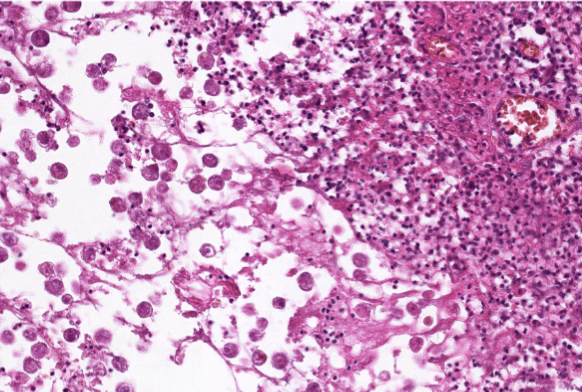

colon cancer